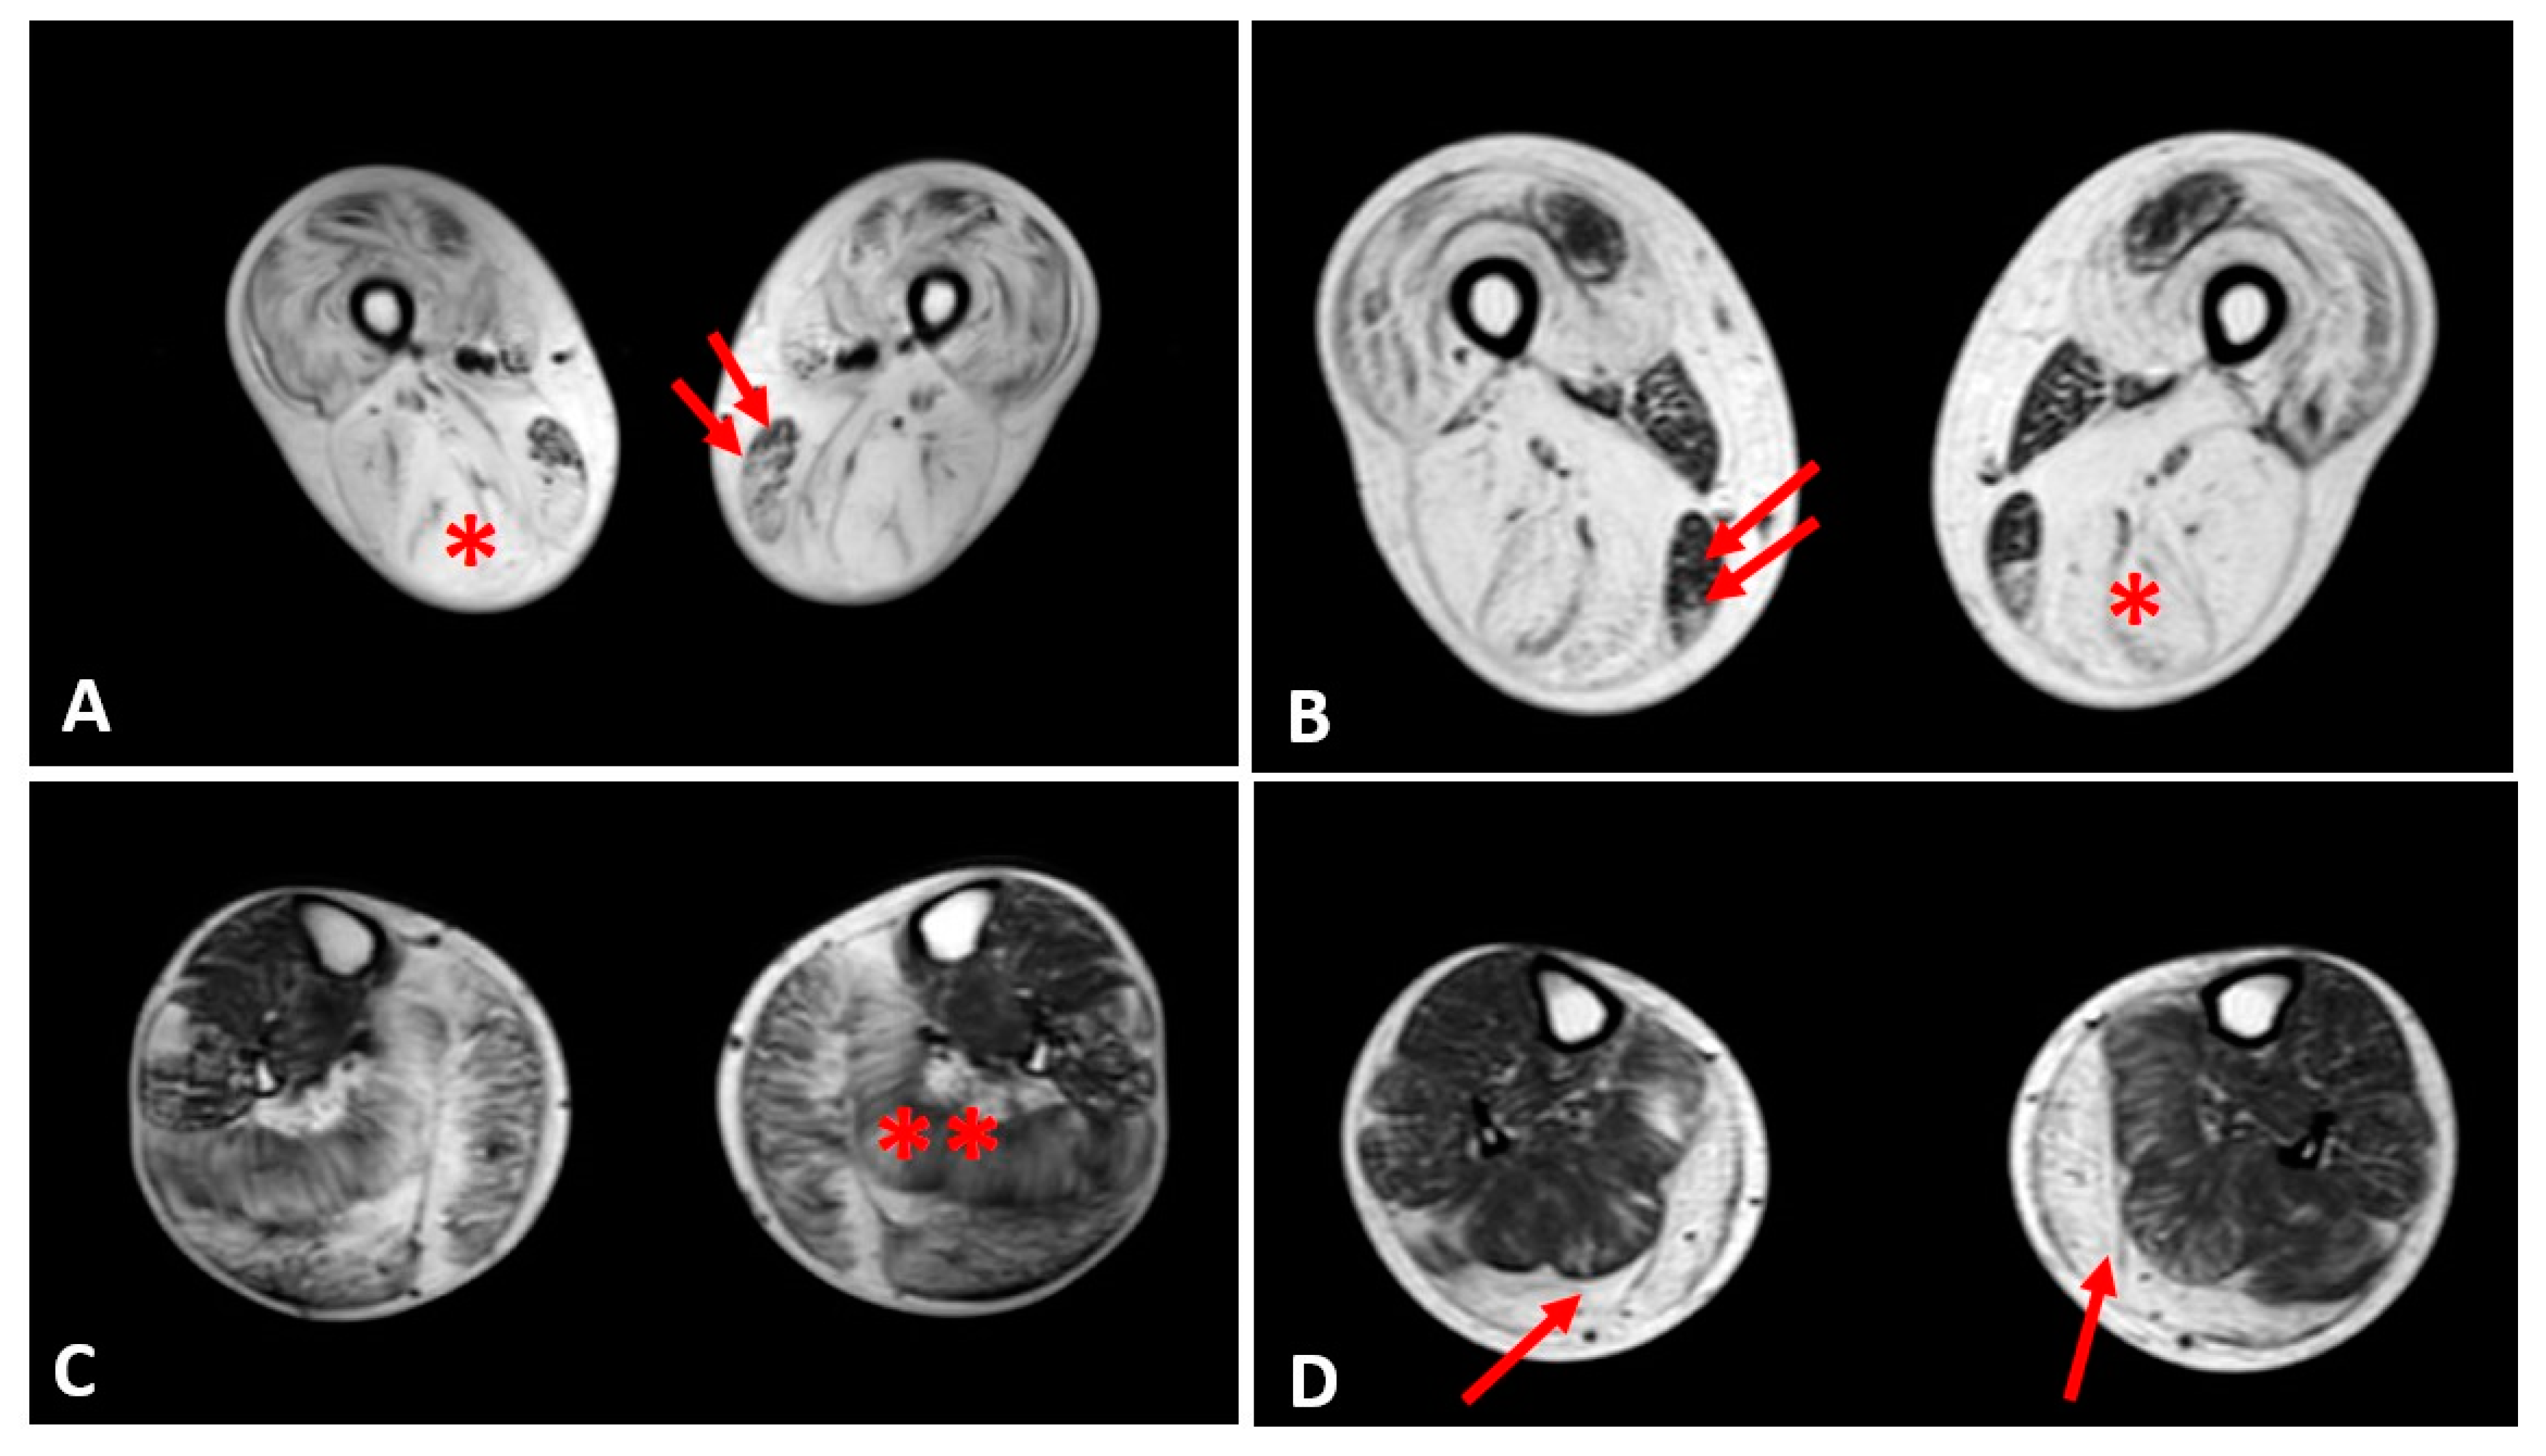

Thigh muscles showed significant fatty infiltration of muscles in the anterior and posterior compartment in patient 1 and patient 2 who were treated with steroids. Both quadriceps and posterior hamstrings muscles were equally affected; only gracilis and sartorius muscles were spared in these two patients (Figure 4).

Figure 4.

Evaluation of fibrofatty infiltration in lower limbs in two steroid-treated BMD patients. T1-sequences of thigh muscles shows marked atrophy of quadriceps and hamstrings (single asterisk) in both patients sparing of gracilis (double arrows) and sartorius muscles (A,B). In leg muscles, gastrocnemius and soleus muscles (double asterisk) presented advanced fatty and connective tissue infiltration in patient 1 (C), whereas marked atrophy and moderate fatty infiltration were observed in gastrocnemius muscles (single arrow) of patient 2 (D).

In the other patients, the thigh muscles were normal or slightly compromised, except for patients 7 and 8, in whom the fatty tissue infiltration in hamstring muscles reached Mercuri score 2a.

The posterior leg compartment was mostly affected in the two patients treated by steroids, showing severe fatty infiltration in gastrocnemius muscle. In the anterior leg, tibialis anterior was slightly involved; these 2 patients showed a Mercuri score 2a (Figure 4).